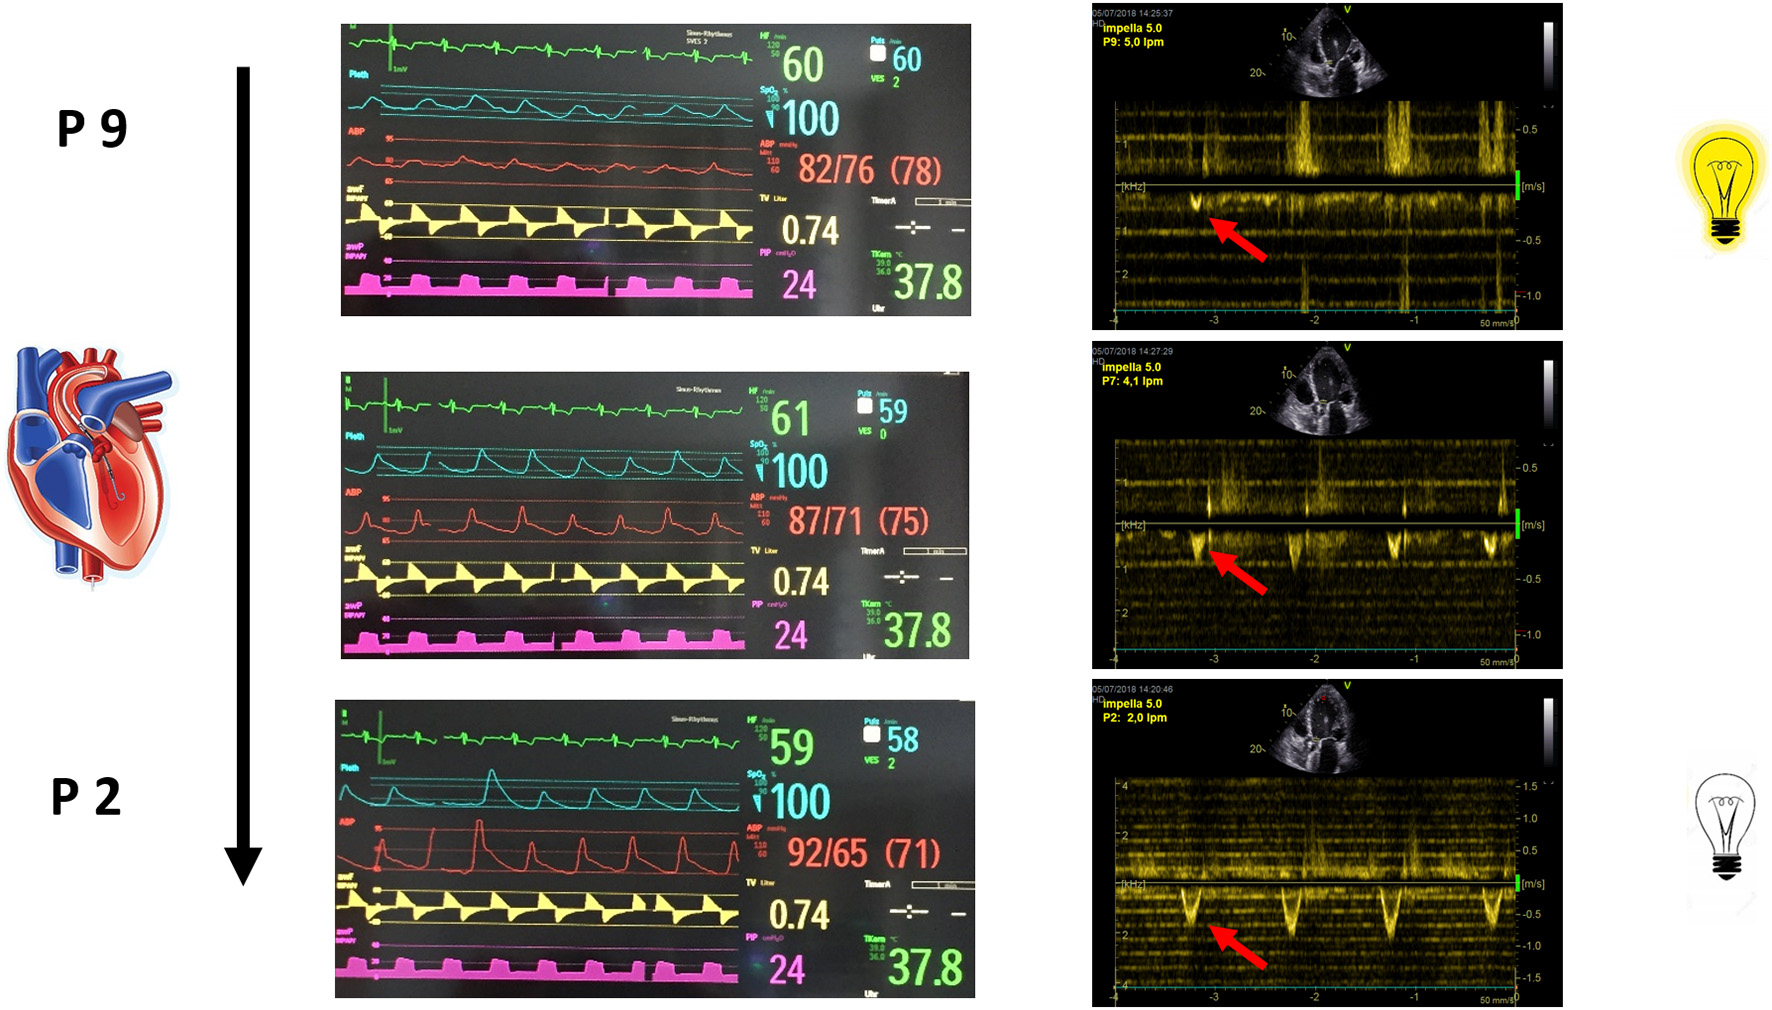

Baseline measurements are acquired during full Impella unloading as well as during minimal Impella support (P2). To assess LV function during exercise-like conditions, steady-state PV loops are additionally acquired during handgrip at minimal Impella support over 2 min. Figure 1A (and related.gif files as online supplement) shows original tracings of Impella patients during rate change (from full unloading P8 to minimal support P2 and back) with the typical shift of the loops on the xy plane. Figure 1B (and related.gif files as online supplement) shows two patients with different study outcomes: on the right a patient who profited from unloading, showing no or minimal increase of LV end-diastolic pressure (EDP) during handgrip; on the left a patient who had an abnormal pronounced increase of LV EDP during handgrip, as a sign of blunted contractile reserve. With regard to LV EDP, a novel Impella system has been introduced on the market, called smart assist (Figure 2). This system displays real-time LVEDP, mean arterial pressure (MAP), and cardiac power output (CPO) directly on the Impella console, and will probably play an important role in the future, especially with regard to the weaning process.

Step Two, Impella Rate Reduction, Including Daily Minimal Flow Echocardiography

After step one evaluation is completed, Impella rate is decreased in single steps (e.g., P8 to P7, and so on) with the goal of achieving half of the baseline support with stable hemodynamics. At every rate, echocardiographic changes in the abovementioned three compartments as well as hemodynamic responses (blood pressure, heart rate, lactate and central venous O2 saturation) are monitored over the total procedure. If, at any period in the weaning protocol, RV or LV distension occurred or significant hypotension or increase in heart rate is observed, the weaning protocol is stopped and Impella support is returned back to full flow. Overall, Impella support should be reduced by single 8–24-h steps and then daily re-evaluated. During the daily, minimal flow (P2) echocardiographic examination following parameter and their acute changes will play a major role in the clinical decision-making process:

Left heart. LV chamber dimensions, LV EF and E/e'. In order to discontinue the Impella support, LVEF should be above 30–35%. A LVOT VTI increase with a lower level of Impella support is the Doppler echocardiographic demonstration of bi-ventricular recovery (Figure 5).

Figure 5

The increase in LVOT VTI with a lower level of Impella support is the Doppler echocardiographic demonstration of bi-ventricular recovery.